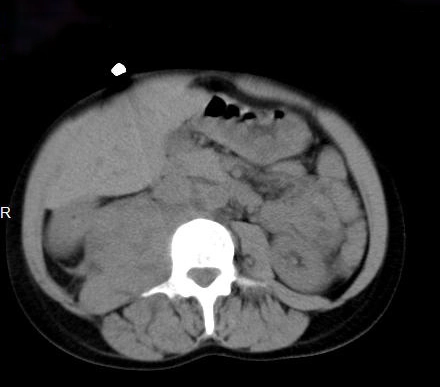

Các khối u cơ